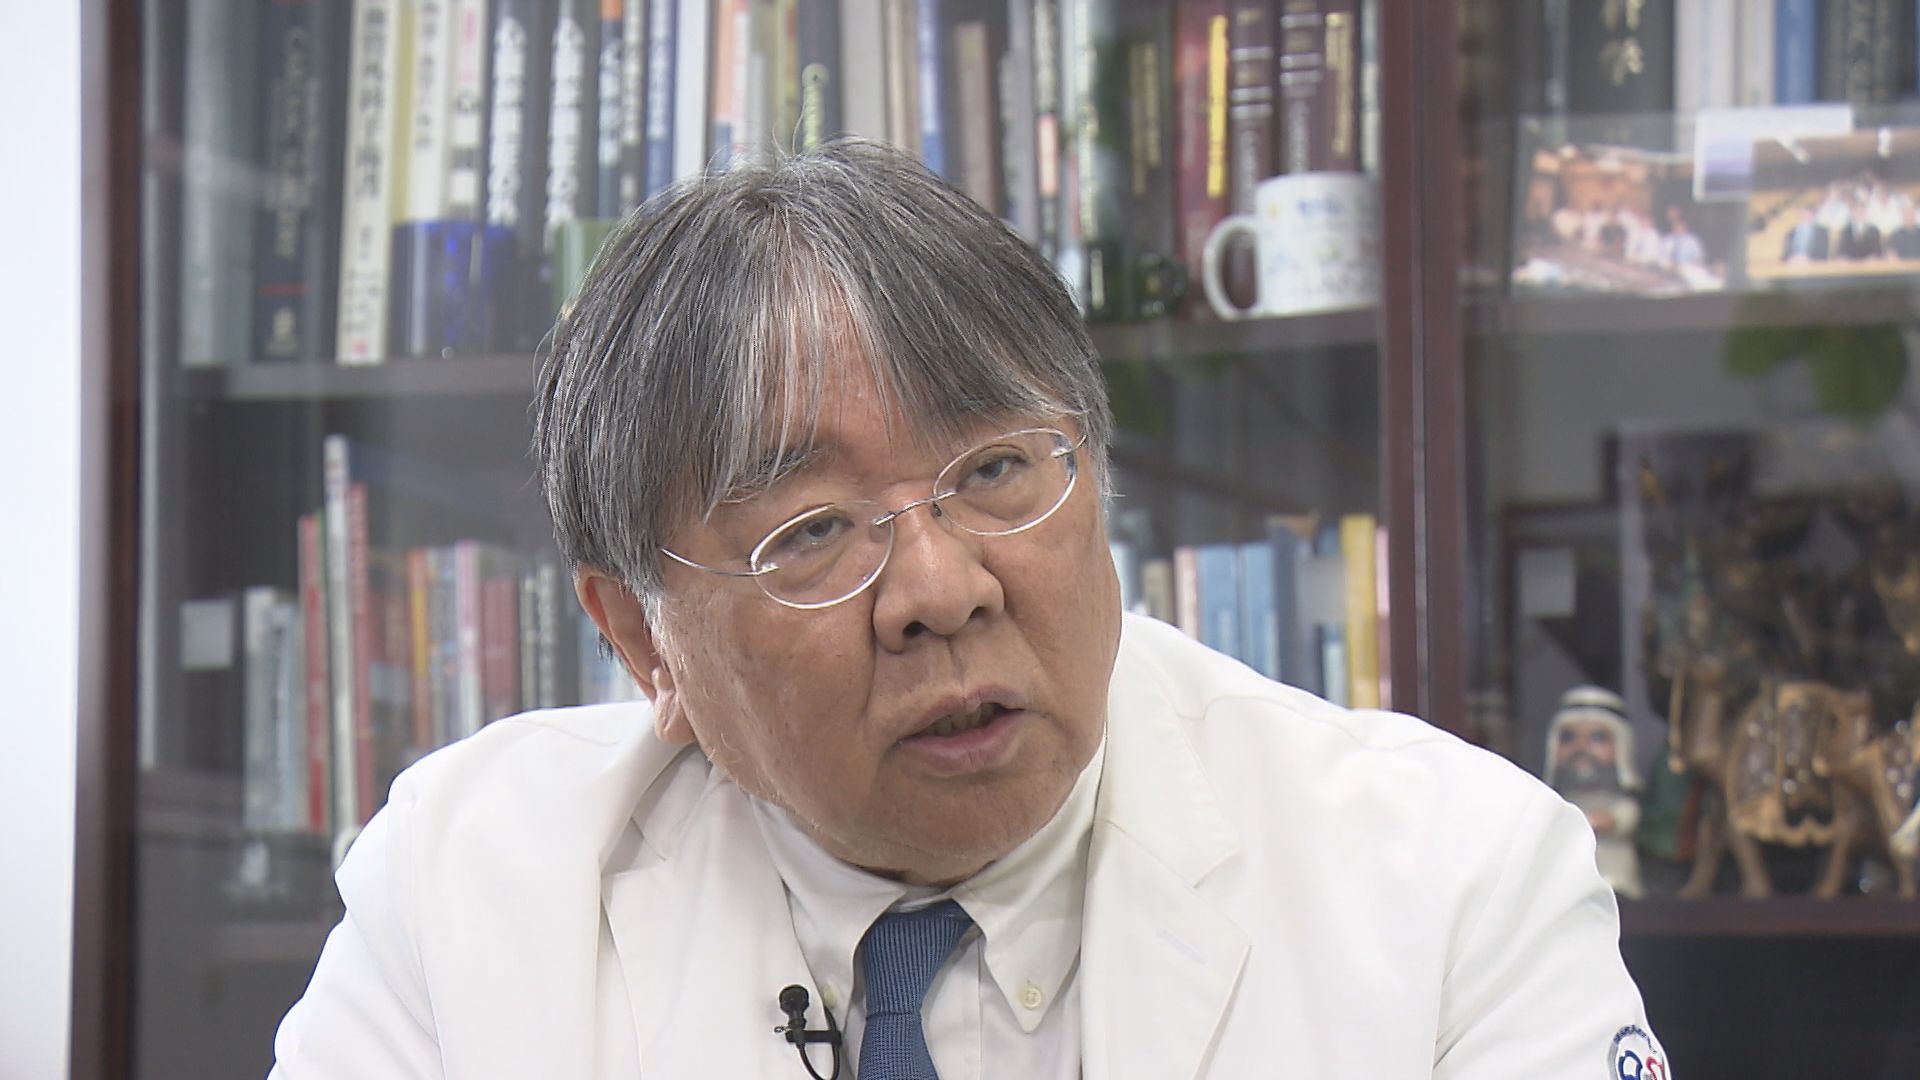

iPS心臓モデルを手がけるのは、大阪大学発のベンチャー企業「クオリプス」。

最高技術責任者を務めるのが大阪大学の澤芳樹特任教授(70)だ。

そんな中で、澤教授は治療の選択肢がなくなる『ノーオプション』の状態になった患者に施す治療はないかと模索し、「再生医療」の研究開発にたどり着いたという。

■救える命があるはず たどり着いた「再生医療」研究

【大阪大学・澤芳樹特任教授】「心臓移植を待つ患者さんを数百人診てきました。人工心臓を装着するのですが、この治療だけでは、半年とか1年はいい成績が出るんですけど、3~5年と経ってくるとですね、合併症が増えてくるんです」

「もう本当に厳しい状況の中で、そういう治療を我々は行いながら、移植待機中の患者さんへのドナー提供をどれだけ増やすかという努力もしながら、一方で違う治療の開発をすべきだと考えて、患者さんを治すことができるような再生医療の研究開発を進めてきました。現状の医療でノーオプションだけど、再生医療なら一つのオプションになるという方がいらっしゃるんです」

患者の心臓の筋肉を「再生」させる新たな治療法の確立を目指して、澤教授はベンチャー企業「クオリプス」を立ち上げた。

【大阪大学・澤芳樹特任教授】「医者になった時に、心臓病の人を一人でも救いたいと、自分は努力したつもりです。その中で治せない患者さんがたくさんいらっしゃって、医師として苦しくつらい思いをしました。新たな方法を用いて助けることができたらという思いで、何十年も研究を続けてきたわけです」

「我々の治療が、ほんとに実現したら、最終的には『心臓病で死なない世界』ができるのではないかと私は思っています。それをどう実現していくかですね、これからまだまだ乗り越えなければならないステップがあるわけです。新たな若い人たちが、この研究の道に入ってもらって、一人でも多くの命が助かる道を、一緒に進めてほしいと思っています」

「『万博で見た時、あんなもんだったけど、人に使える、臨床に使えるようになったね』と、そういうところまで進化するように、若い人に刺激を与えたいというのが、僕が一番やりたいことです。iPS心臓モデルを見た人の中から『ゲームチェンジャー』が出てきてほしいんです」

澤教授は、50年後にはiPS心臓の移植が当たり前になる時代がやってくるのではないかと期待している。